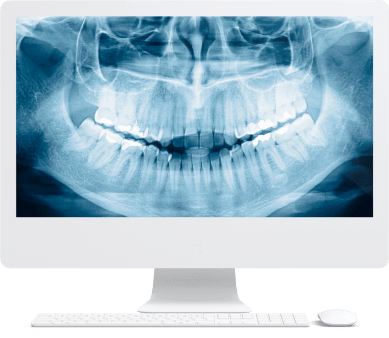

Зубы за 1 день за 5776р. в месяц

По уникальной методике

Установка

за 1 день